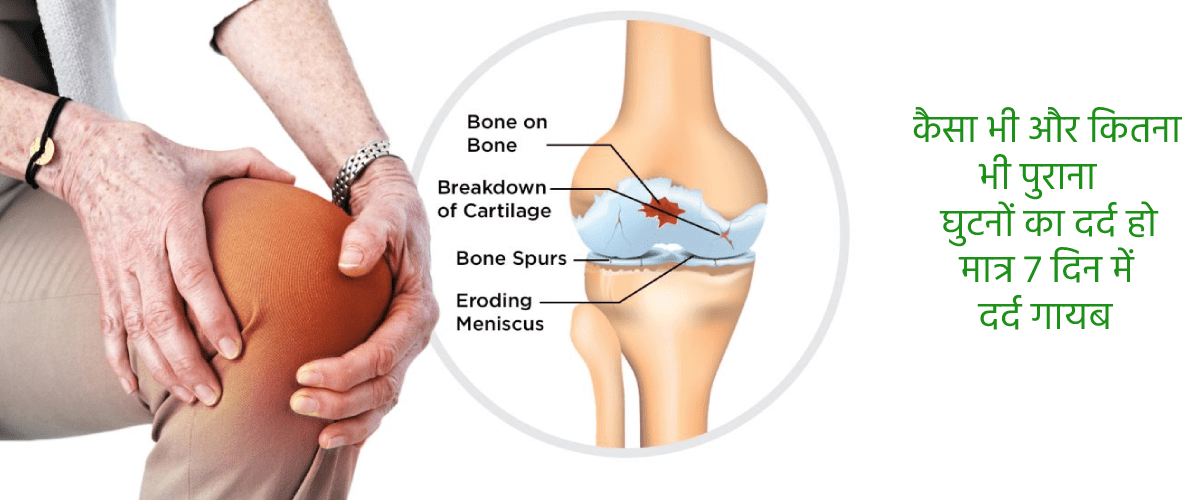

सुमित त्यागी जी का कहना है कि वह कुछ ही महीनों में ऑस्टियोकांड्रोसिस के गंभीर से गंभीर मामले को भी ठीक कर सकते हैं। जहां तक जोड़ों के दर्द का सवाल है, यदि उनका ठीक से इलाज किया जाए तो यह 7 दिन में भी ठीक हो सकता है। यह अपनी 8 साल की प्रैक्टिस में कई बार ऐसा करके दिखा चुके हैं। यह हमारा सौभाग्य था कि "हर उम्र में स्वास्थ्य जोड़" टीवी प्रोग्राम के लाइव ब्रॉडकास्ट के तुरंत बाद हमें सुमित त्यागी जैसे बड़े एक्सपर्ट का इंटरव्यू करने का मौका मिला।

वास्तव में यह सीक्रेट तो बहुत ही सरल है। हमें दर्द की जड़ को समझने की जरूरत होती है। आज मेडिकल एनसाइक्लोपीडिया में ऑस्टियोकांड्रोसिस और ऑस्टियोआर्थराइटिस के करीब 150 कारण दिए गए हैं, लेकिन वास्तव में इन सब का परिणाम एक ही होता है। जोड़,रीढ़ की हड्डी और गद्दी की लचक चली जाना, जिससे दर्द होता है। आपको पता है यह क्यों होता है? इसलिए क्योंकि रक्त का प्रवाह ठीक से नहीं होने के कारण ये घिस जाते हैं।

यही तो इसका सीक्रेट है। हम रक्त प्रवाह वापस ठीक करके जोड़ों का इलाज करते हैं।